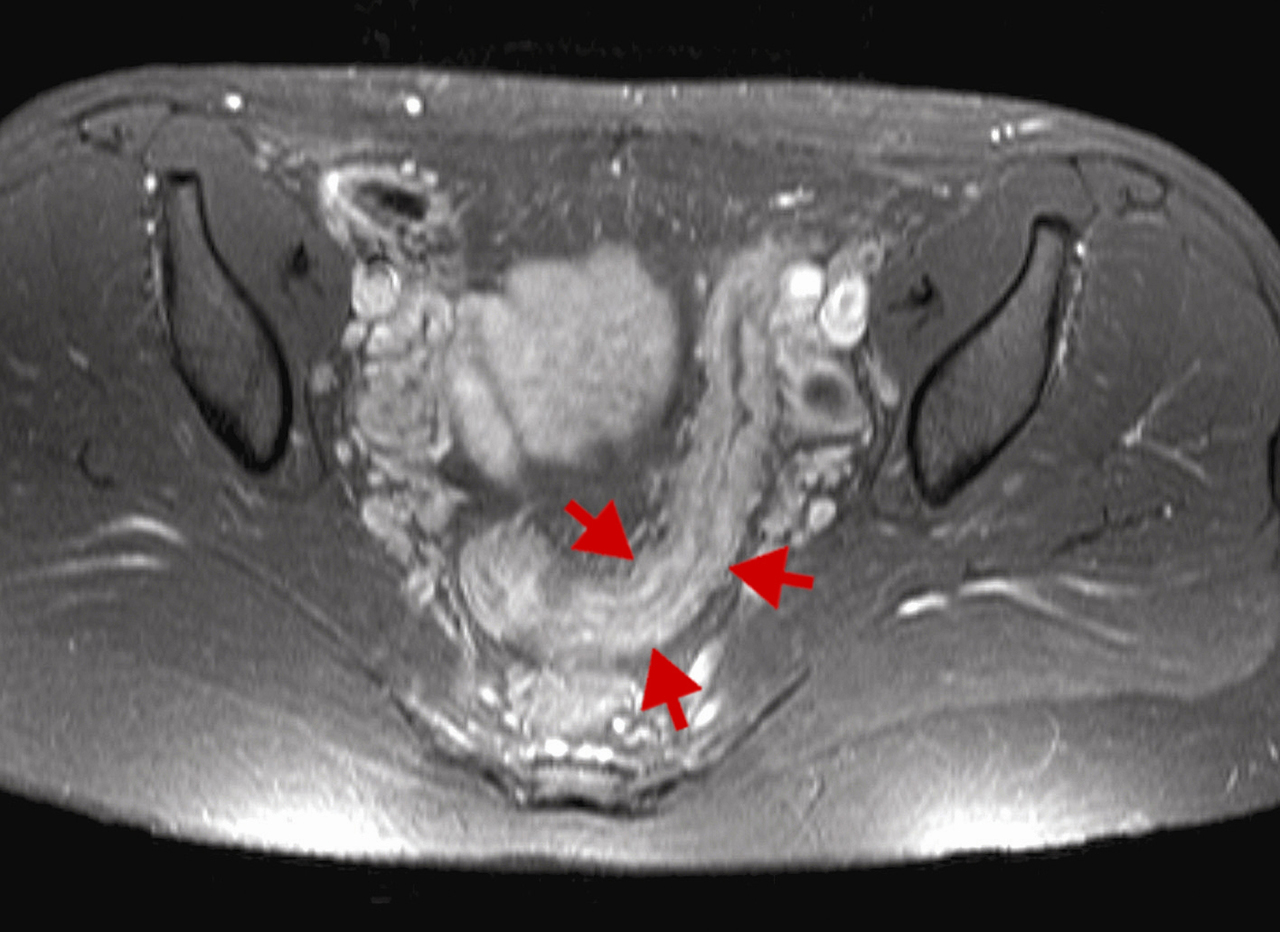

IRM en séquence pondérée T1 avec injection de gadolinium et saturation de graisses revelant un épaississement inflammatoire du sigmoïde (flèches rouges).